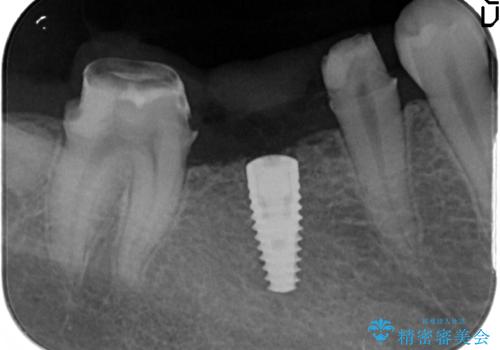

- 虫歯で歯を失い、インプラント治療を希望され来院されました。

吸収した骨を造骨にて補い、インプラントによる機能回復を計画します。

歯を失ってからの時間が経過し骨が吸収してしまっていても、造骨を行うことで予知性の高いインプラント治療を行うことができます。